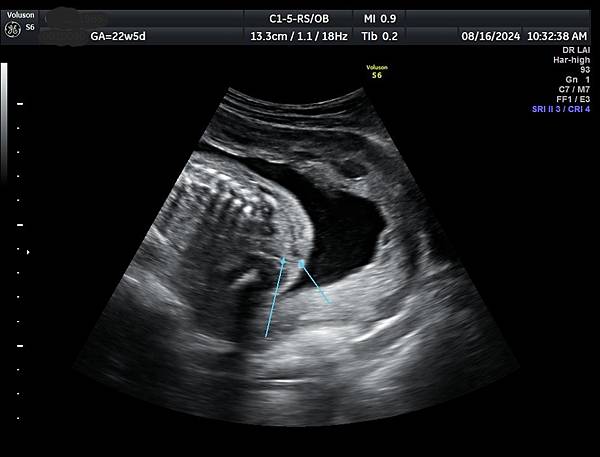

針對部分胼胝體發育不全的診斷,需要非常小心,如果胼胝體只有1/3的個案比較不會是假的,如果是2/3的個案就要很小心判斷是否過度診斷,我喜歡把胼胝體當做第五腦室(CSP )及第六腦室(cavum vergae )的天花板,CSP 與cavum vergae的比例大約2:1,通常CSP 和cavum vergae 都是黑黑的(附圖1),這樣的情況不會量錯,如果cavum vergae呈現白白時(echogenicity),它的天花板就很有可能被誤判不屬於胼胝體,這個問題我已經遇過很多類似的案例,例如附圖2~4是同一個case,圖4沒有疑慮,圖2及圖3很有可能只量到前面2/3比較明顯的部分,而沒有量到圖上的數據。